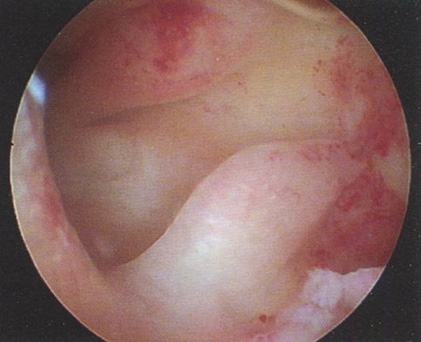

Рис. 3.1. Описание гистероскопической картины:

• полость матки треугольной формы, не деформирована;

• эндометрий бледно-розового цвета, в виде складок и гребней различной величины. При изменениях давления за счет введенного расширяющего раствора отмечаются волнообразные движения эндометрия;

• устья маточных труб не всегда визуализируются.

Заключение: гиперплазия эндометрия. Гистологическое исследование: простая железистая ГПЭ.